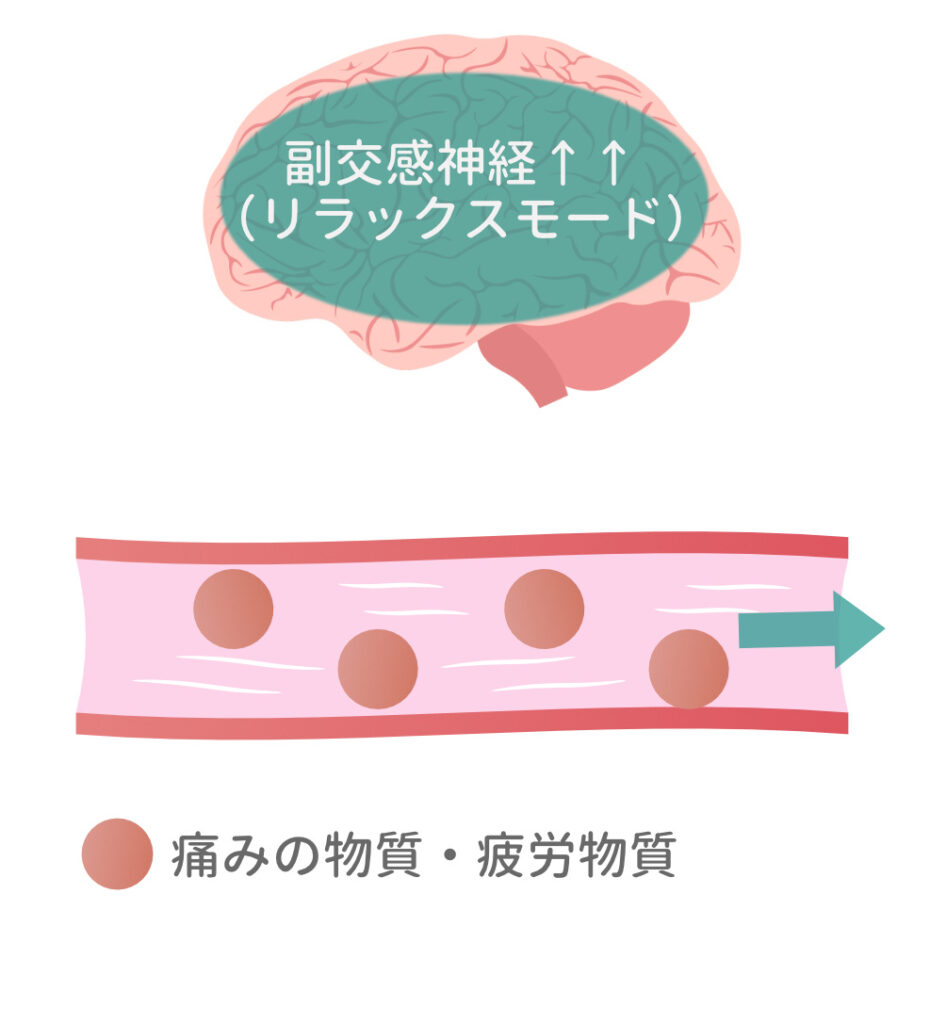

2. 指圧のメカニズム

「痛みのツボ」に5~20秒ほどの圧刺激をくわえてリラックス効果を促します。

▼

副交感神経が活発になり血流が促されると「痛みの物質・疲労物質」が流れやすくなります。

▼

膝を気にせず

外出できるように

かたまった筋肉を、溶かすようにやわらかくしていくイメージです。